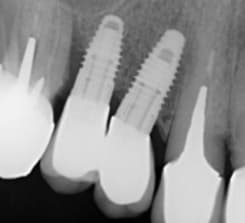

Salut Pluton, peut être pourras tu me dire de quel implant il s’agit. Je t’envoie une radio de l’implant et une photo du pilier (ou plutôt de ce qu’il en reste). Au cas où ce ne serait pas très clair sur l’image, la connectique ressemble à celle du conelog (cone morse associé à une partie cylindrique possédant trois ergots longilignes). Merci d’avance

c'est un Biotech Kontact

http://osseosource.com/dental-implants/product_info.php?manufacturers_id=144&products_id=2524

mais vu la lise osseuse autour de cet implant...amha c'est mort...tu devrais le déposer... donc un bon coup de tourne à gauche et dans quelques semaines tu en reposes un tout nouveau tout neuf....